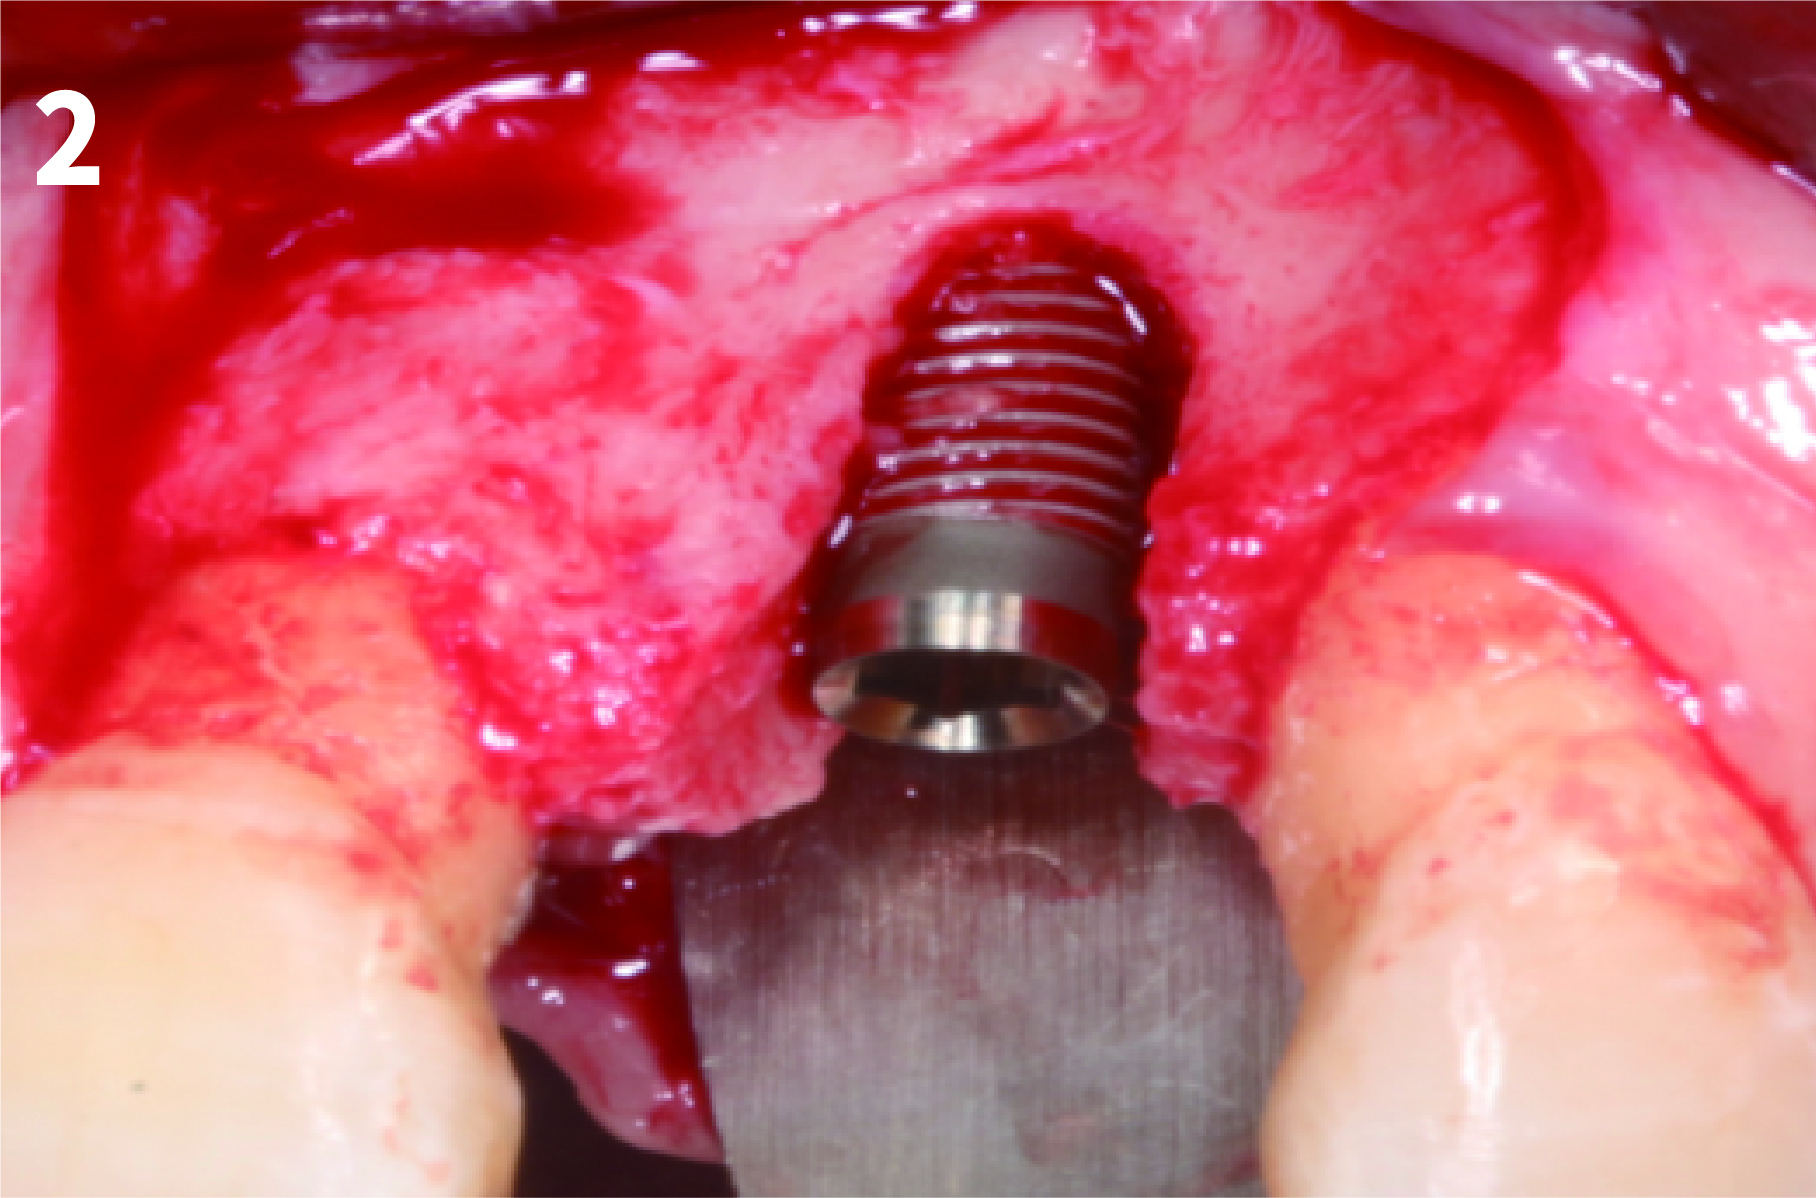

Case 1: Simply Augmented Severe Dehiscence Defect on Anterior Area

2. After exposure the bony defect with mucoperiosteal flap, completely remove the granulation tissue, inflammatory tissue.

4. After wetting the BOSS granules, fill up the defect area with the bone graft.

7. After filling the graft, cover the surgical site with mucoperiosteal flap and should be fixed by sutures. Be sure to completely seal the implantation site to prevent exposure.